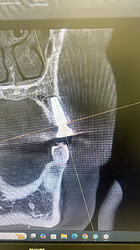

Placed #12 implant today . Looks like I placed the implant too buccally. Should I reposition ? Implant size is 4.3x13mm . Torque-40 ncm.

Definitely don’t remove/reposition and I would suggest stop evaluating placement via CBCT because doing so will almost always show lack of buccal bone. Years ago I heard Scott Ganz lecture about how CBCT “always” underestimates buccal bone… in other words there is “always” more buccal bone present than what appears on the image. As wonderful as advanced imaging is it will never replace direct visualization. Not sure if you placed this guided and flapless but I was taught and I still believe that a person should place a minimum of 100 fixtures conventionally before they resort to AI surgery. In this situation the quality/quantity of the overlying soft tissue is more important than the thickness of the buccal bone anyway. Nice work!!!

Implant was placed free hand after reflecting the flap. Also visually it looked like I had 1.5-2 mm bone . I will double check with perio probe when pt comes back

You did have 1.5-2mm of buccal bone then because you visualized it and no you should not add graft material. CBCT is worthless for evaluating the buccal plate around a fixture and direct visualization doesn’t lie… IMHO CBCT machines are so popular in dentistry because they always justify another procedure with another expense. If that fixture has good surrounding soft tissue then it will be fine even if the CBCT image is accurate which direct visualization has already proven that it is not accurate. At the end of the day soft tissue is far more important for long term success than some radiographic simulation of white stuff that we refer to as bone.